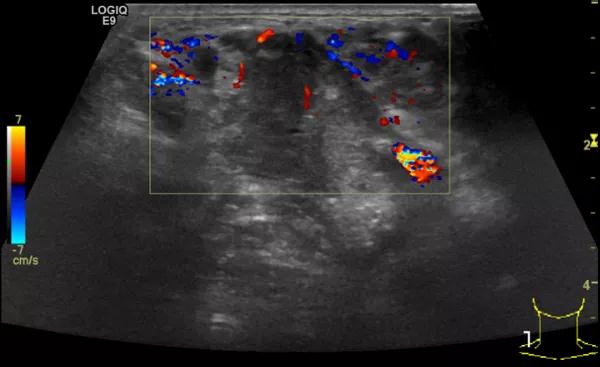

第三例是甲状腺癌患者,双侧甲状腺癌切除术后、碘治疗后一年余效果欠佳,超声显示左颈3区3枚低回声结节,穿刺示甲状腺乳头状癌转移。患者不愿意手术,希望采取局部治疗。对病灶进行液体隔离后采取热消融术,由于淋巴结较小,热消融一分钟左右完全灭活,术后增强影像显示没有脏器充填。

(病例3图例)